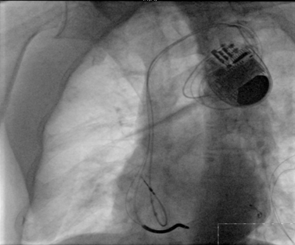

冠状静脉逆行造影